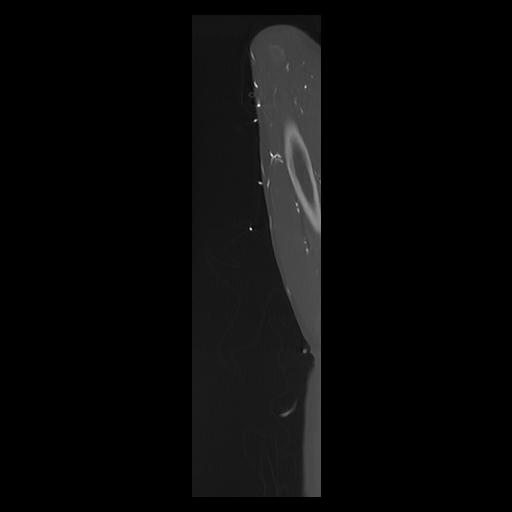

33 PULMON,CE,Sagittal,3.000,PULMON,Sagittal,